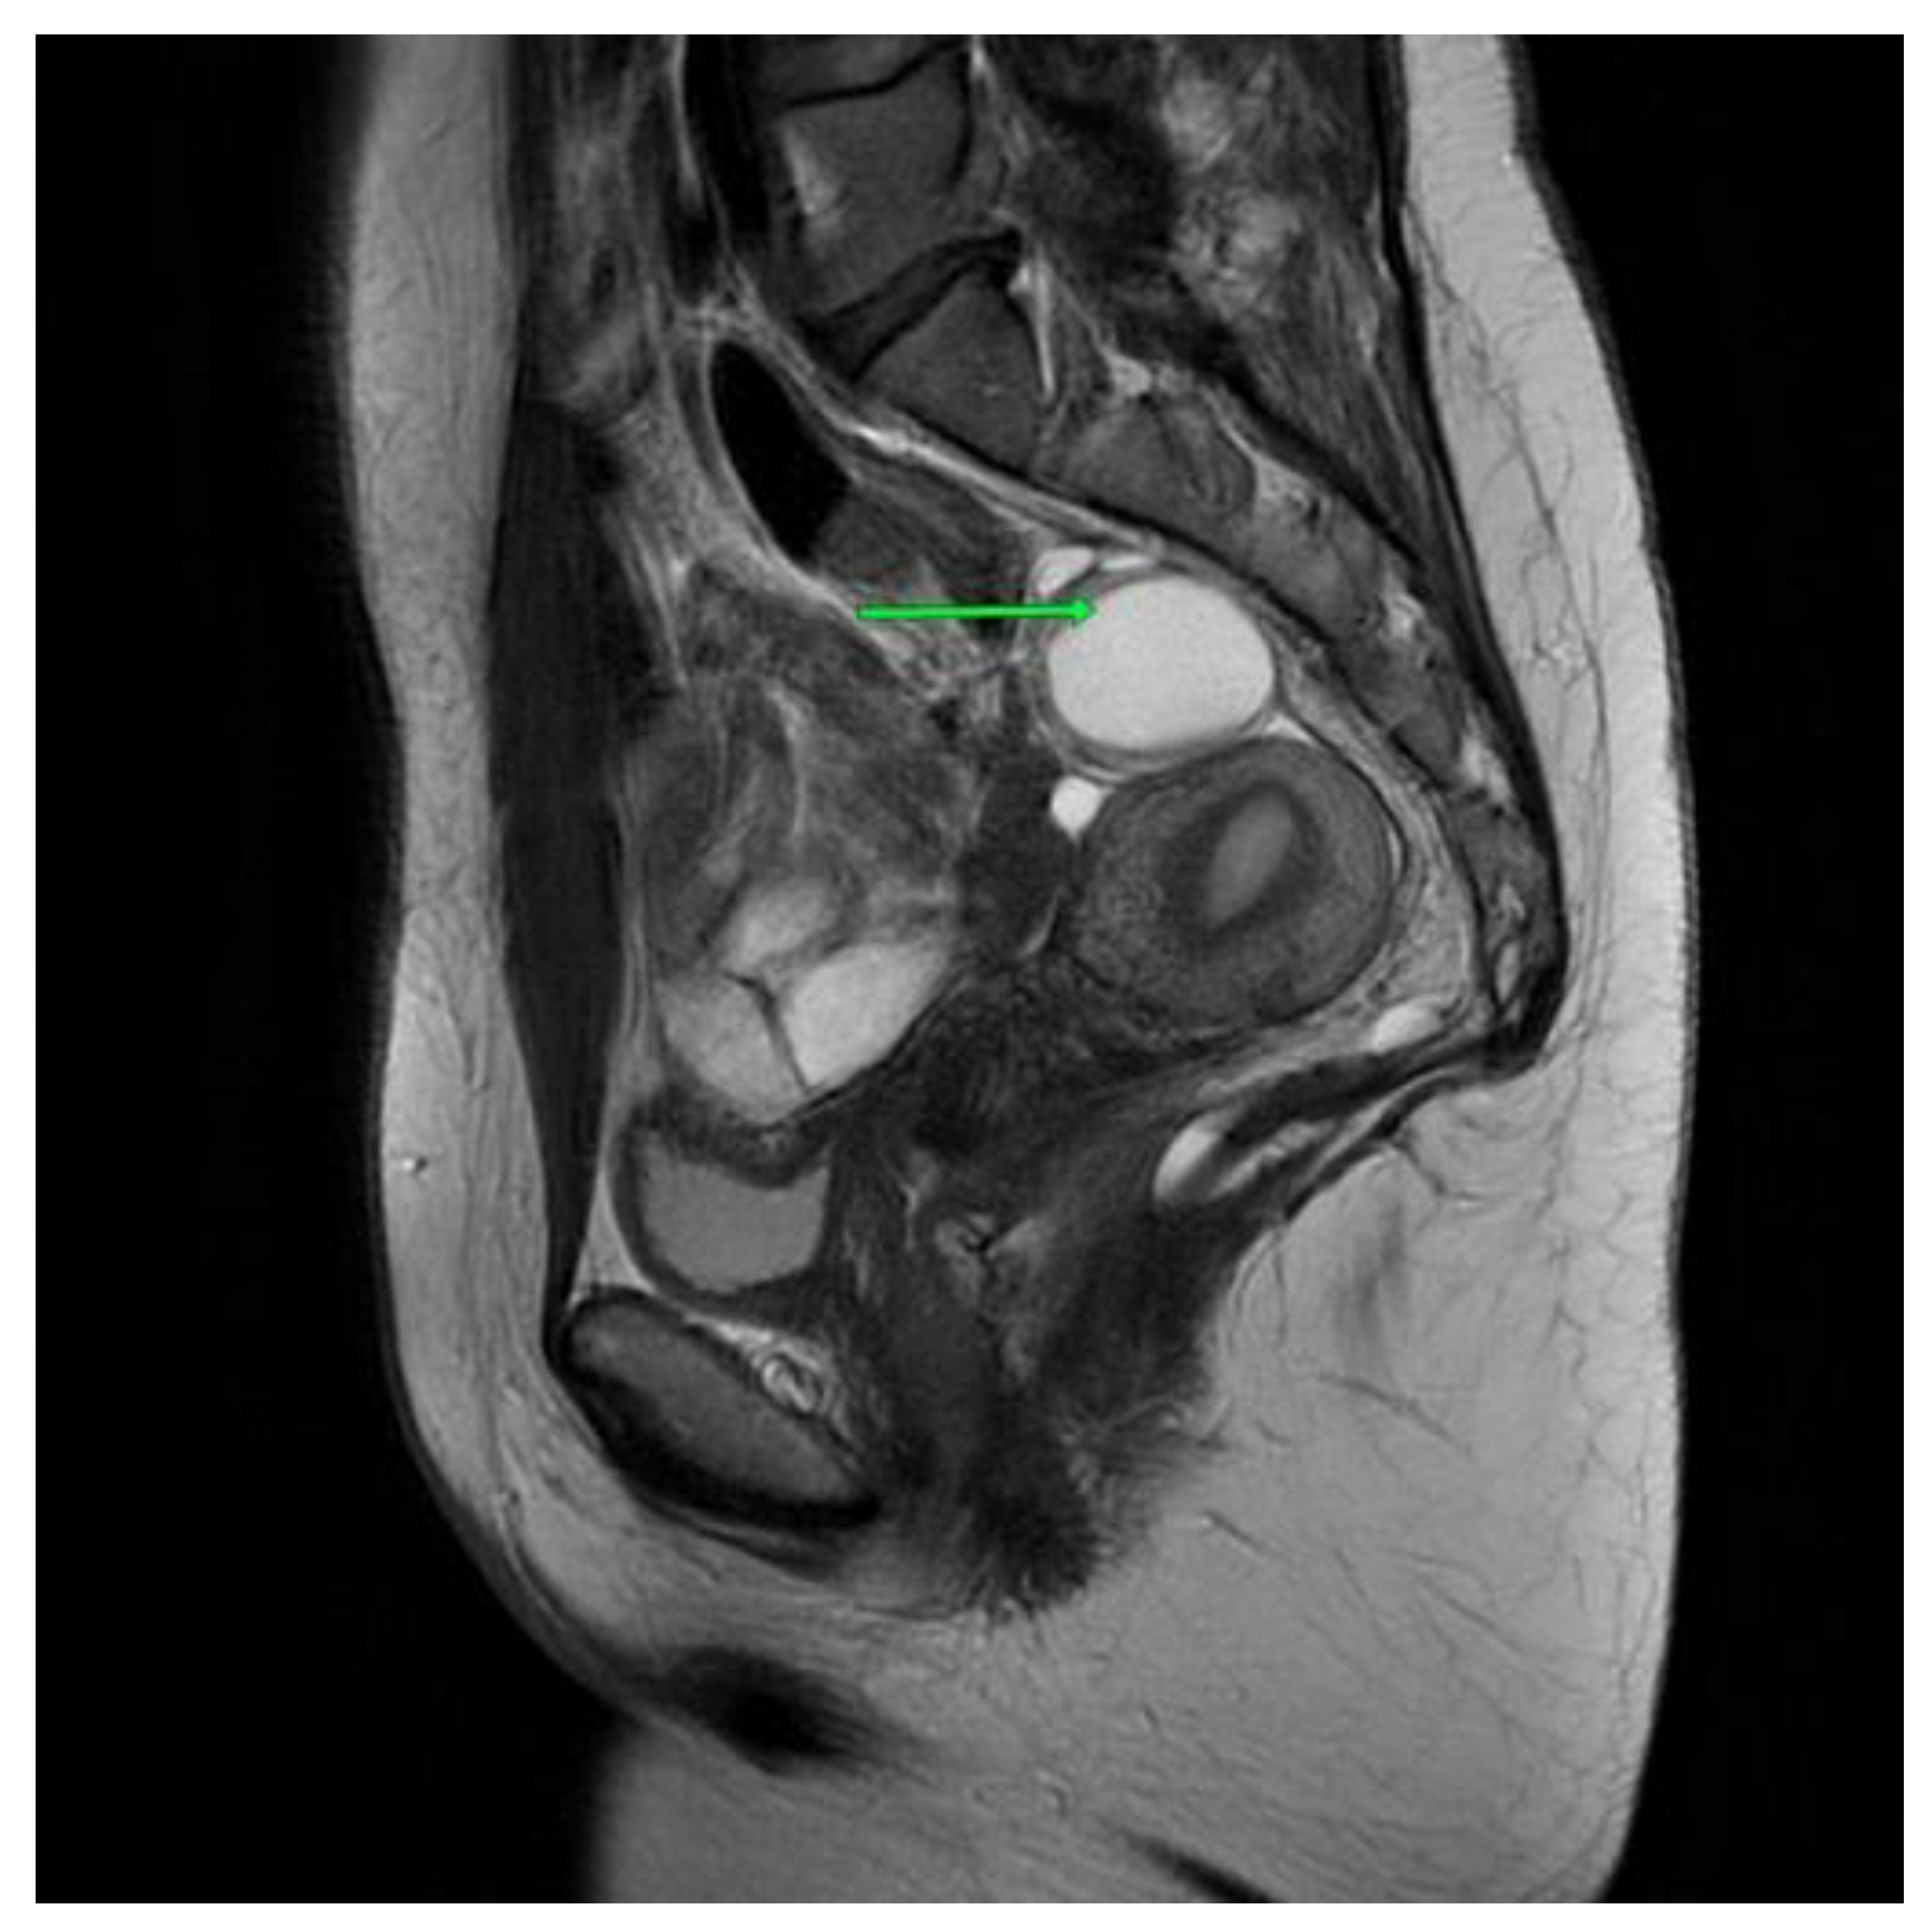

In the first MRI scan, eight months after the procedure, a small amount of fluid was visible in the operated area. Some small cystic, thin-walled structures were also visible, and will be monitored in future imaging [Figure 5].

Figure 5. Second patient MRI scan of the lesser pelvis eight months after the procedure.